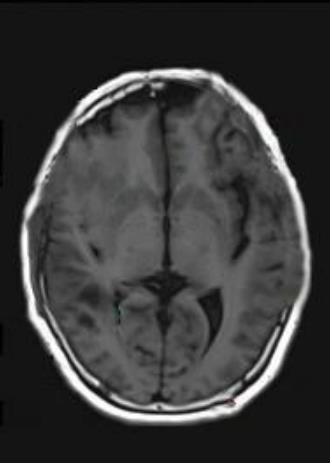

• 肿瘤样脱髓鞘病变报道3例

2023, 48(5):614-617. DOI: 10.13406/j.cnki.cyxb.003183

摘要 (95) HTML (24) PDF 1.29 M (241) 评论 (0) 收藏

摘要: